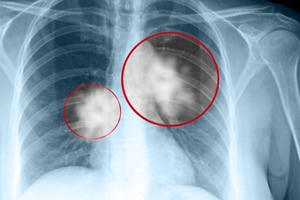

Ung thư phổi là một trong mười loại ung thư thường gặp và là nguyên nhân gây tử vong hàng đầu tại Việt Nam. Theo số liệu thống kê ở nước ta, trung bình một năm có khoảng 20.000 ca mắc ung thư phổi/năm.

Bệnh ung thư phổi có hai loại: Ung thư phổi tế bào nhỏ và ung thư phổi không tế bào nhỏ. Trong đó bệnh nhân mắc ung thư phổi tế bào nhỏ thời gian sống không kéo dài quá 6 tháng.

Bệnh ung thư phổi vô cùng nguy hiểm, có đến 70% người mắc bệnh ung thư phổi tử vong chỉ trong vòng 1 năm sau khi phát hiện.

Ung thư phổi là loại ung thư gây tử vong hàng đầu, gặp phổ biến ở độ tuổi từ 45 đến 70.